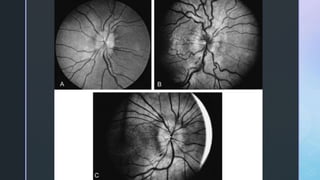

• #26Ā A, Very early papilledema-disc shows slight hyperemia and blurring of the peripapillary nerve fiber layer at the superior and inferior poles of the disc. B, Early papilledema-disc is hyperemic and mildly swollen. Note the inferior peripapillary nerve fiber hemorrhages. C, disc is moderately swollen with obscuration of all borders, a peripapillary halo, and several small splinter hemorrhages adjacent to the disc margins at 7 and 10 o'clock.